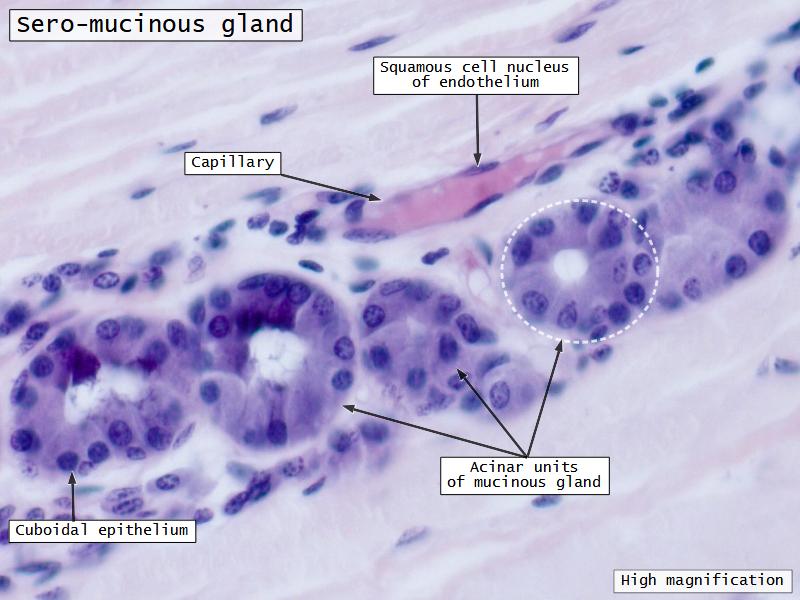

Trachea

Bronchi - Transitions

- Intrapulmonary bronchi

- Irregular cartilage

- Respiratory epithelium

- Glands

- Bronchioles

- NO glands - goblet cells -> secretory cells

Clara cells

Read more about the use of eponyms.